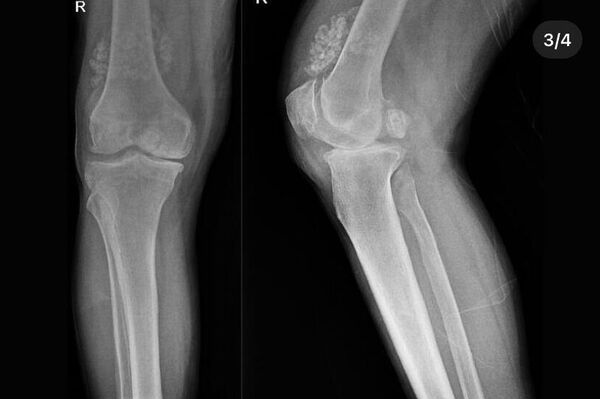

Tetkiklerde, hastanın özellikle diz eklemi çevresinde halk dilinde “eklem faresi” olarak bilinen 41 “multipl sinovial kondromatozisi” tespit edildi.

Eklem faresi (loose body) özellikle diz eklemi çevresinde görülmekle birlikte kalça, dirsek ve diğer eklemlerde de görülen, ufak parçalardan oluşan cisimlerdir. Eklem çevresinde eklem sıvısı ya da sinoviyumda görülen kıkırdak ya da kemik parçalarıdır. Eklem farelerinin boyutları birkaç milimetreden birkaç santimetreye kadar olabilir.

Eklem faresinin tespiti Röntgen kullanılarak kolay bir şekilde yapılabilir. Ciddi boyutlarda olan serbest cisimlere cerrahi tedavi uygulanır ve parçacık bulunduğu bölgeden direk alınır. Cerrahi tedavi sonrası kişilerin fizik tedavi süreci başlar. Şişlik, ağrı ve kas zayıflığı, kas kısalığı gibi durumlarda dokuyu eski haline getirerek tedavi süreci tamamlanmış olur.